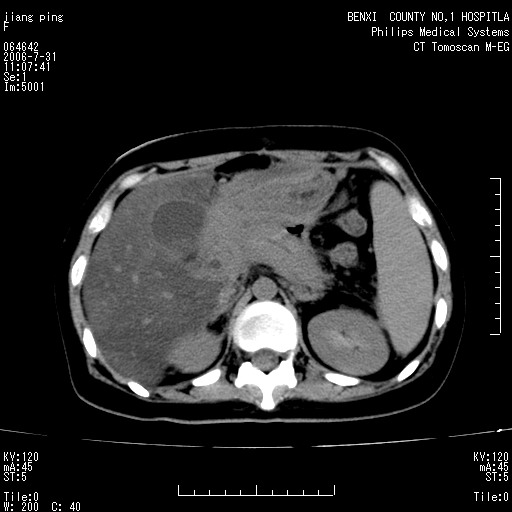

以下是引用晓杰在2006-8-1 9:01:00的发言:[br]支持营养不良导致脂肪肝。[br]胰头增大界限不清,考虑为胰腺炎破坏十二指肠粘膜、肠壁增厚、肠腔狭窄,并与胰头粘连所致

以下是引用jiajie在2006-7-31 20:34:00的发言:[br]支持营养不良导致脂肪肝。[br]胰头增大界限不清,考虑为胰腺炎破坏十二指肠粘膜、肠壁增厚、肠腔狭窄,并与胰头粘连所致。